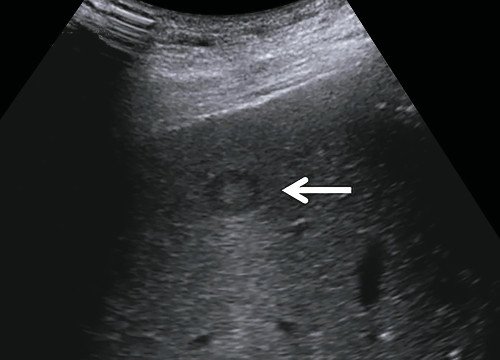

Как выглядит доля Риделя на УЗИ печени